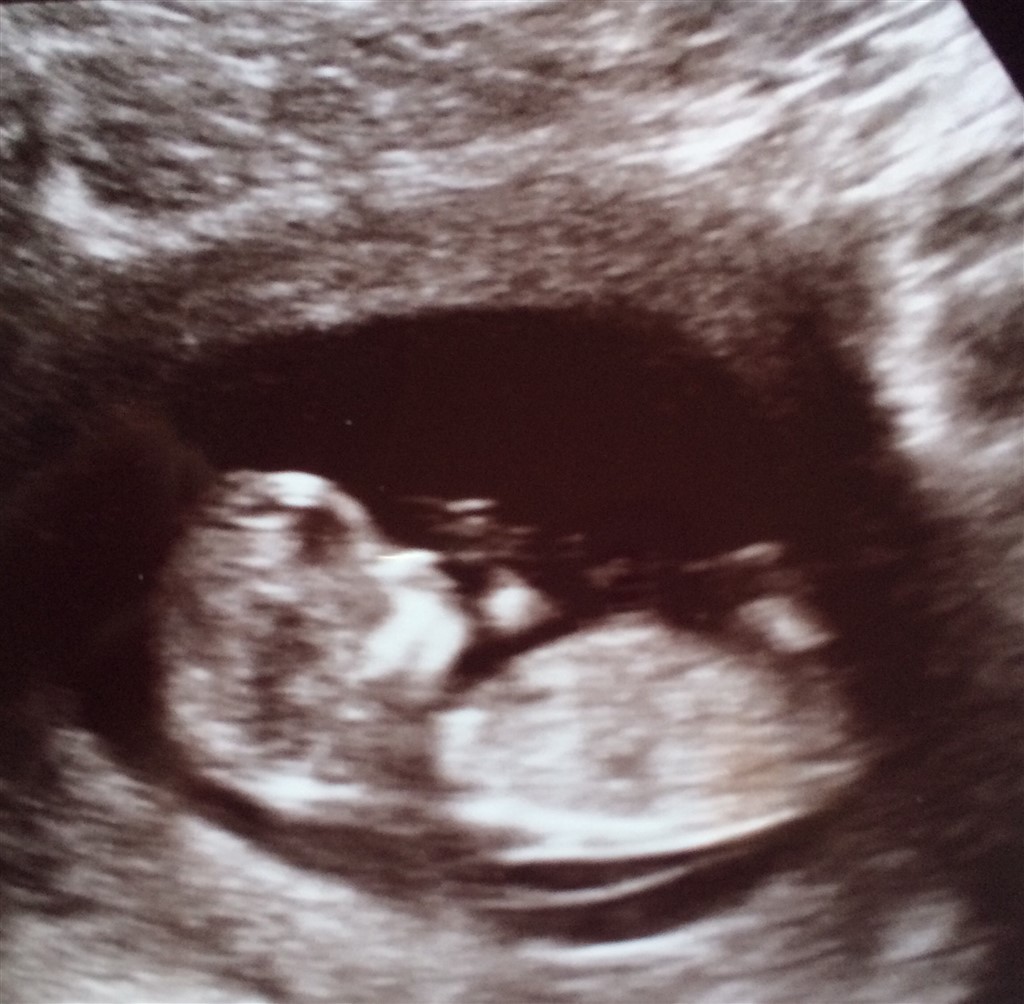

jeg er gravid i 13 uge!

Vi var til nf i tirsdags og det var en sund og rask livlig bebs der lå derinde, så det gør jo en rigtig glad!

satte lige et billede ind af bebs